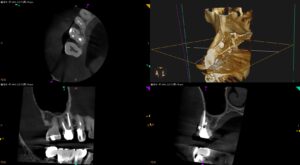

クロロホルム(C-solution)を使用するのは害悪か?+Gutta Percha Point除去のNi-Ti Rotary File, 何がベスト?!〜#3 Re-RCT

近年、Gutta Percha Pointを除去するためのNi-Ti Fileが多く紹介されている。 しかし私はその存在には従来から懐疑的だ。 理由は、 私はクロロホルム(C-solution)で古いGutta Perc … 続きを読む クロロホルム(C-solution)を使用するのは害悪か?+Gutta Percha Point除去のNi-Ti Rotary File, 何がベスト?!〜#3 Re-RCT